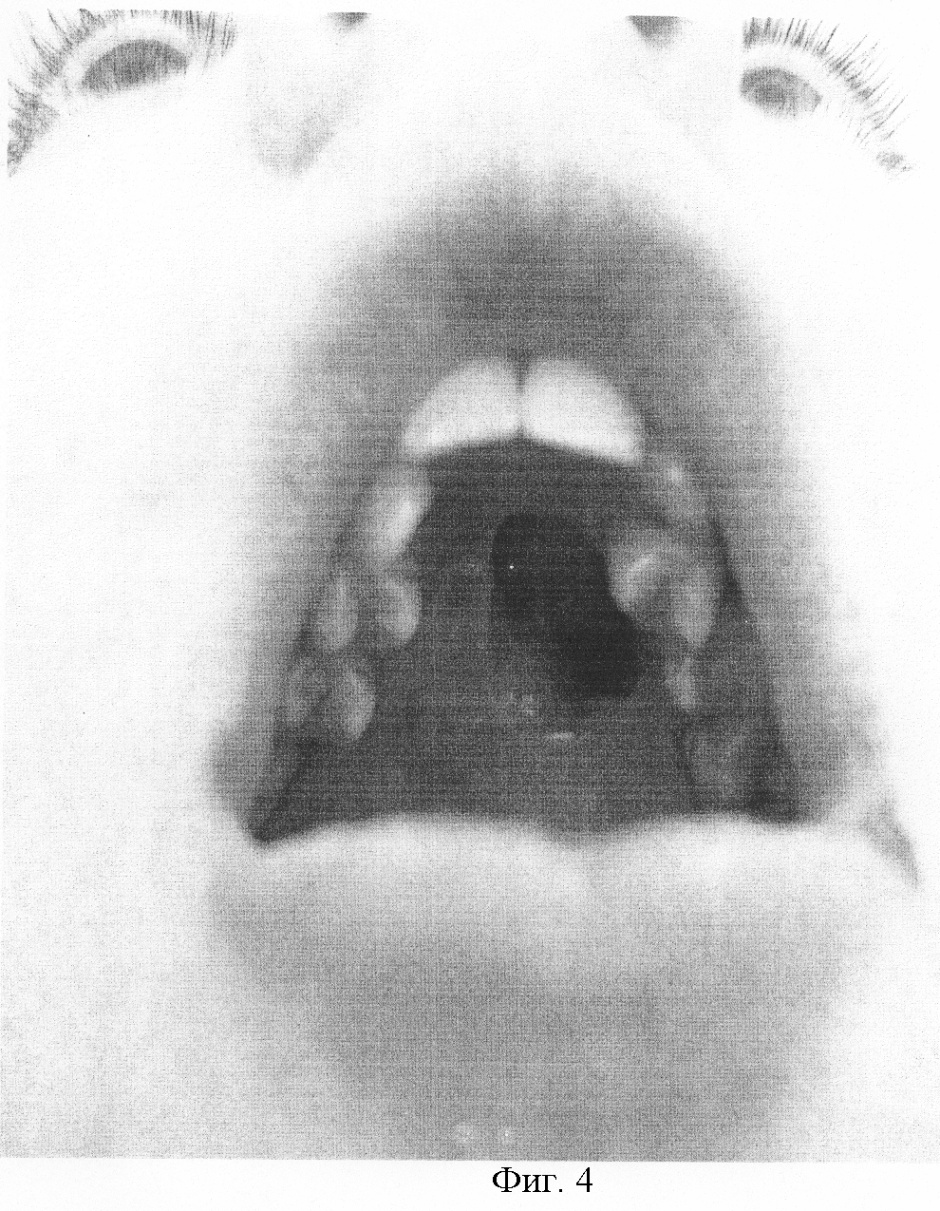

Задачей предлагаемого изобретения является разобщение в послеоперационном периоде носовой и ротовой полостей, улучшение носового дыхания за счет полного закрытия дефекта неба (фиг.4). Это предполагает улучшение функциональных результатов лечения за счет восстановления функции питания и речи, что позволяет полностью реабилитировать пациента.

Результаты лечения показали, что наступило разобщение в послеоперационном периоде носовой и ротовой полостей, улучшение носового дыхания. Это привело к улучшению функциональных результатов лечения за счет восстановления функции питания и речи, что позволило полностью реабилитировать пациента (фиг.3).